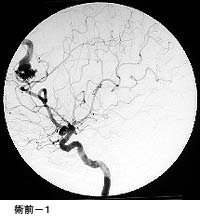

(1)破裂脳動脈瘤に対するGDC(コイル)塞栓術

*術後 コイルにより動脈瘤が写らなくなりました。